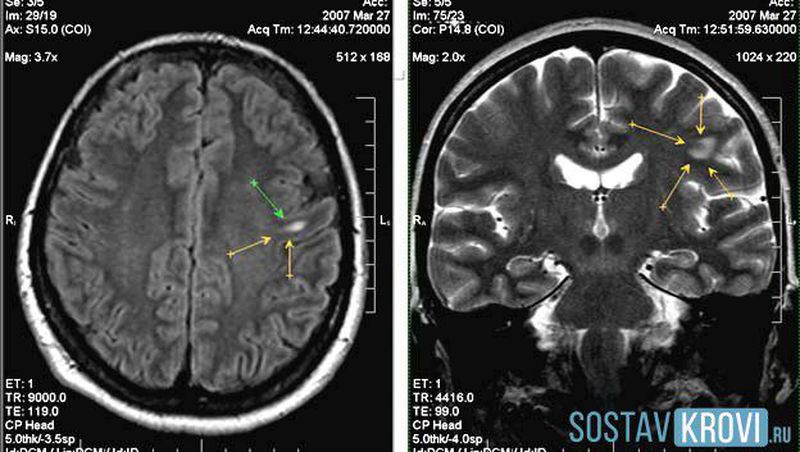

Brain hemorrhage?

Hemorrhage in cortex

Hemorrhage

Barin hemorrahg